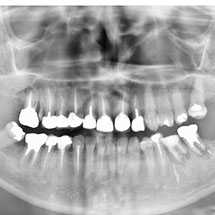

Panoramique dentaire

Il permet d’étudier la formule dentaire (nombre et position), la structure des dents et leur environnement (parodonte). Il permet de visualiser le fond des sinus (sinusite), et les articulations temporo mandibulaires (arthrose, déplacements).

On recherche surtout des lésions dentaires, des dents incluses, des kystes, des granulomes (infections), des anomalies osseuses ou des fractures.

Chez l’enfant, on analyse l’évolution de la dentition.